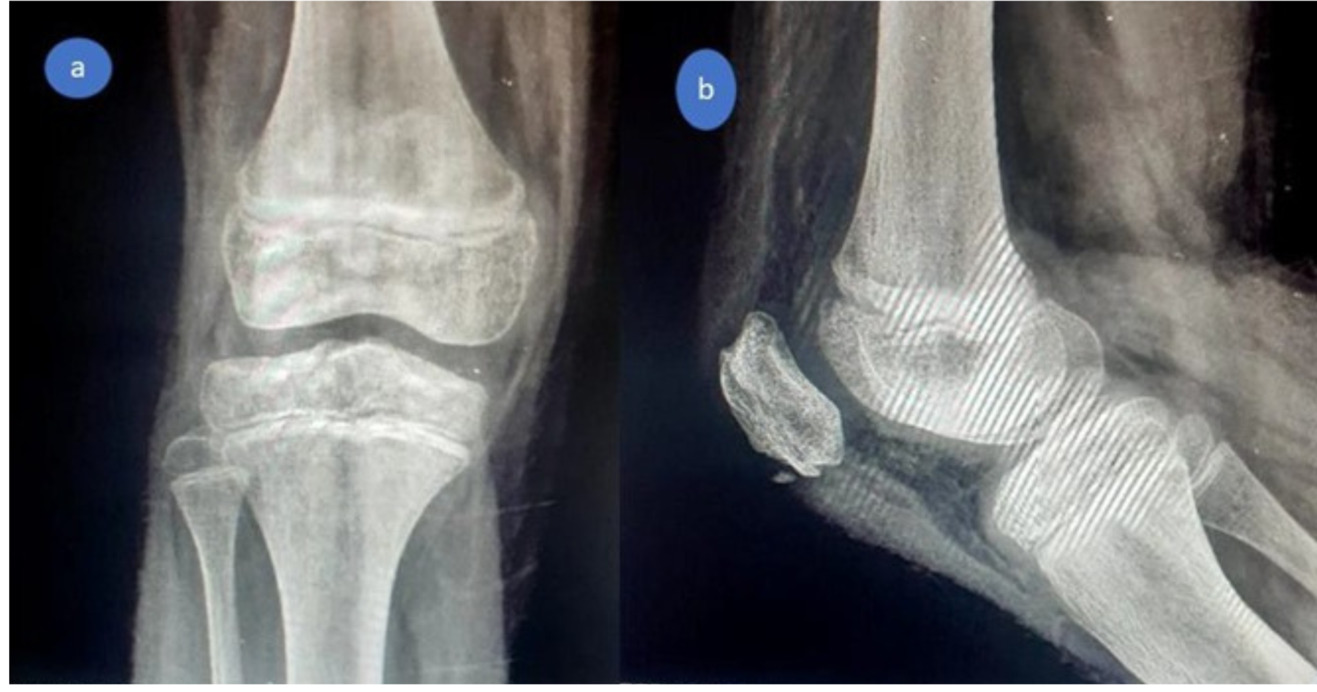

Postoperative radiographs demonstrated satisfactory reduction and fixation (Figures 7,8).

By three to four months, both patients had achieved full knee ROM, restoration of quadriceps strength, and radiographic evidence of complete fragment healing (Figures 9, 10). Return to normal daily activity occurred between the third and fourth months, with clearance for sports and play at six months.

At final follow-up—12 months for Case 1 and 18 months for Case 2—both children were asymptomatic, with full ROM, normal quadriceps power, and no growth-related complications. Radiographs confirmed a well-centered patella with complete bony healing (Figures 11, 12).